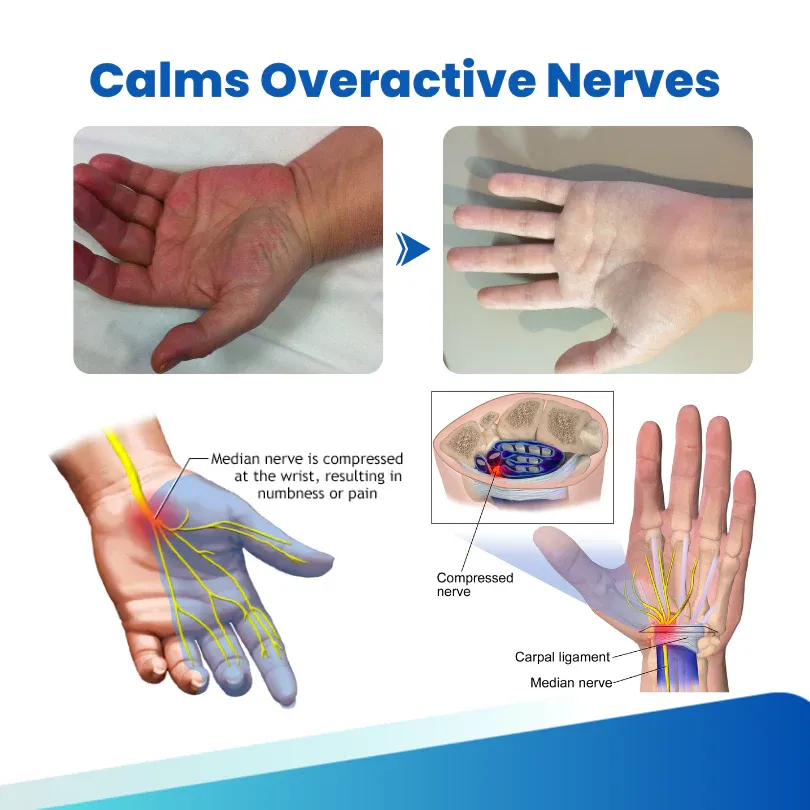

Calms Overactive Nerves: Lidocaine delivers instant numbing relief while Capsaicin gently retrains hypersensitive nerves — reducing the abnormal pain signals behind burning, tingling, and numbness.

Restores Natural Comfort: With Methylcobalamin (B12), MSM, and Alpha Lipoic Acid working together to repair damaged nerve tissue and boost circulation, sensation returns to normal — so you can walk, rest, and move freely again.